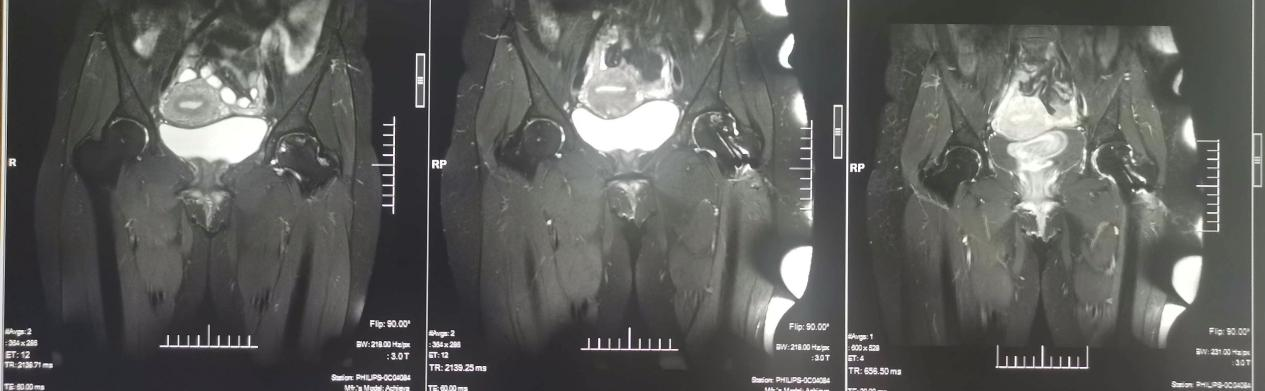

一位23岁女性患者术前术后及末次随访核磁共振图像,可看出病理在逐渐逆转

杨振东医师说:“任何的组织坏死,包括股骨头坏死,因其不可逆性,一直都是世界性难题。但我们骨科开展的这项技术,却是在帮助患者逆转这个病理过程,为什么能逆转,在于提供了血供。”